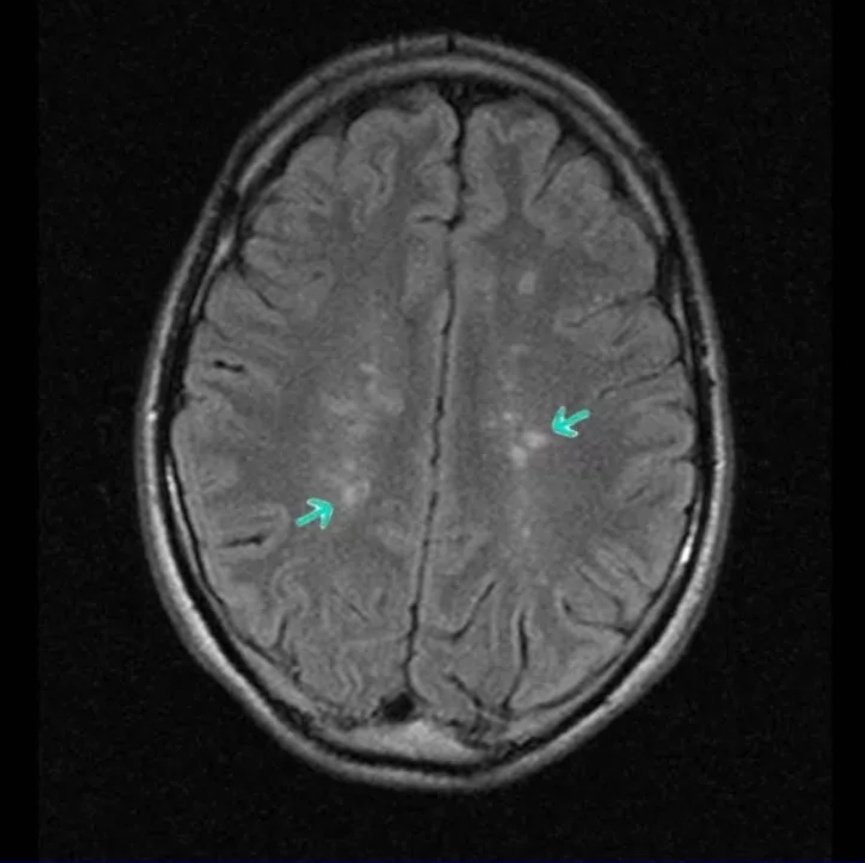

На магнитно-резонансной томографии глиоз о обнаруживается на T2-взвешенных и FLAIR-изображениях: гиперинтенсивные (белые) участки из-за повышенного содержания воды в зоне рубца.

Очаги чаще локализуются в белом веществе, реже — в сером.

Они могут быть различной формы и размера: от мелких точек до обширных областей.

А здесь представлены результаты томограммы пациентки с лёгкими когнитивными нарушениями- жалуется на снижение памяти и забывчивость.